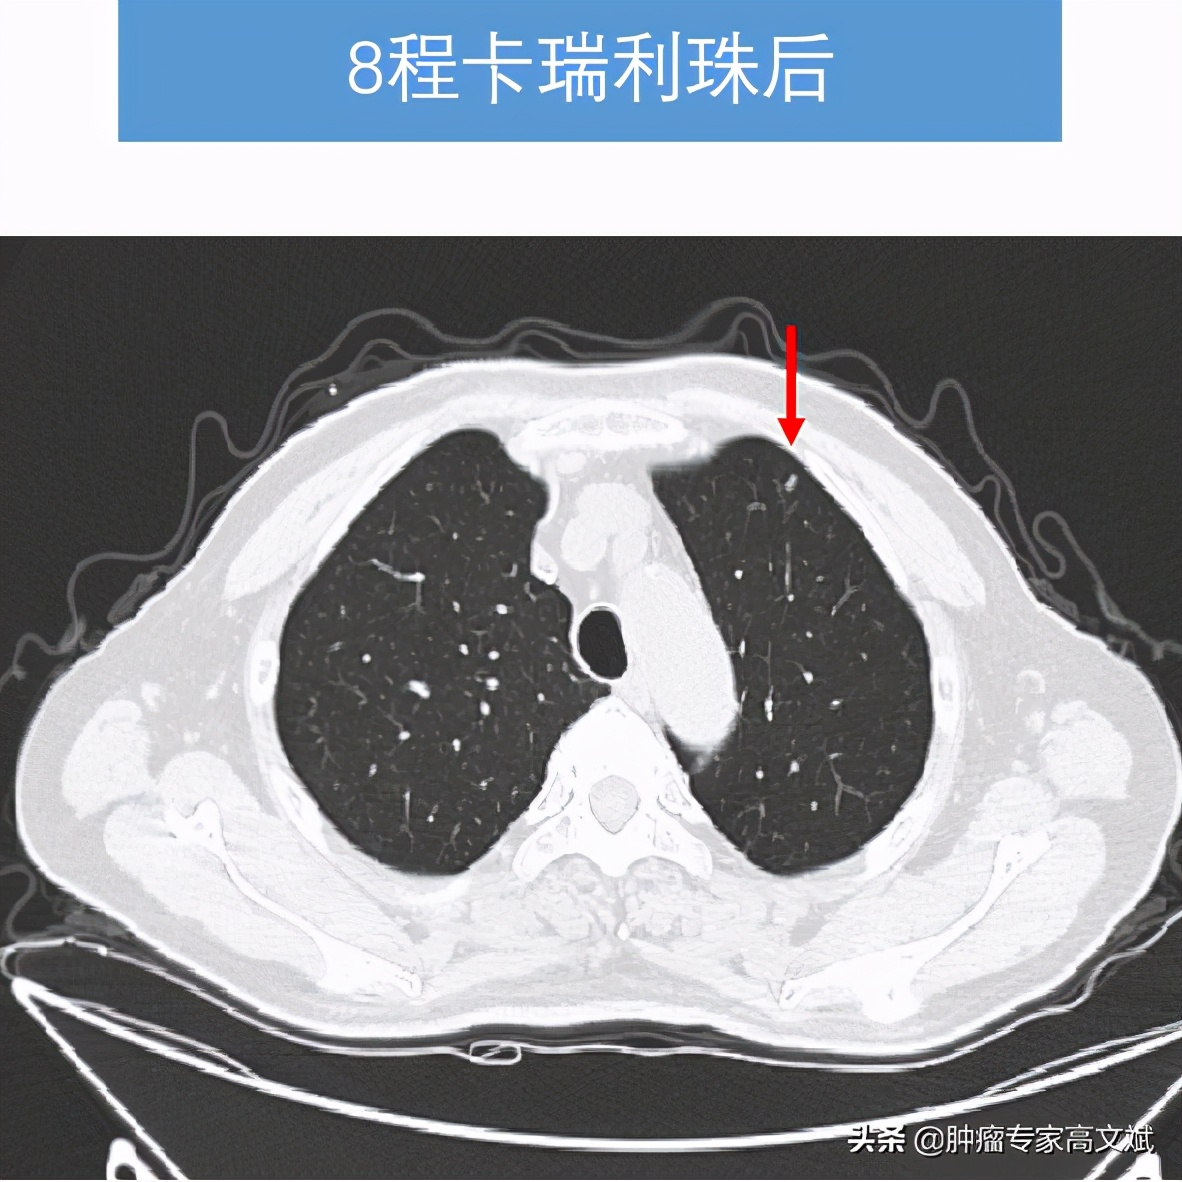

看着患者的一般情况还好,所谓的身体状况不佳主要还是前边治疗的不良反应所导致的。我们还是决定给患者实施一个单药的免疫治疗来控制肿瘤的生长,又不过分增加患者的不良反应。就这样患者也接受了我们的建议,我们为患者实施了国产的免疫制剂卡瑞利珠单抗(艾瑞卡)200mg,每2周一次使用。让我们没有想到的是,患者治疗2个周期以后,肿瘤标志物AFP出现了陡坡样的下降,肝脏疼痛也出现了缓解,每天躺在床上的老陈已经开始下床活动,饮食量等情况也明显的改善,对于治疗患者也有了明显的信心。就这样,治疗了8个周期以后,老陈的肝脏肿瘤明显缩小了,肺内转移灶也有消失,肿瘤标志物则是更早地恢复了正常,止痛药也完全的不再使用了。对于老陈来说,剩下的事情就是每月来罗湖医院肿瘤科输注两次卡瑞利珠单抗(艾瑞卡)就可以了。